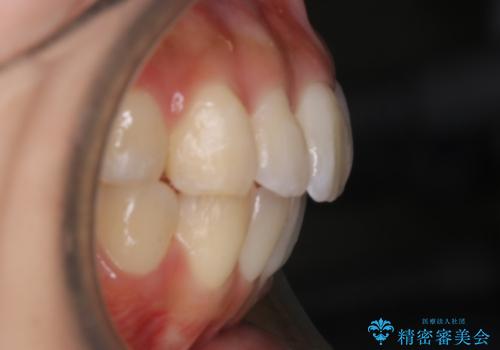

前歯部に特にガタつきが見られ、正中もズレている状態でした。

術前・術後の笑った時の歯の見え方の変化にも注目してみてください!